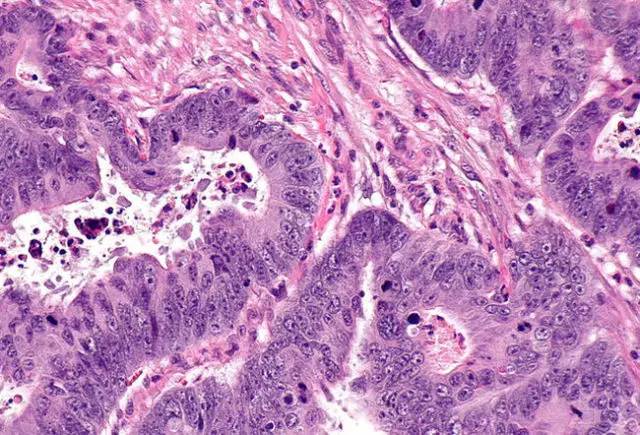

直腸腺癌屬于直腸癌的一種,是指齒狀線以上至乙狀結(jié)腸與直腸移行部之間的腺癌,占結(jié)直腸癌的75%~85%,是消化道常見的惡性腫瘤。我國直腸癌的發(fā)病率占大腸癌總發(fā)病率的60%~70%,但是病因至今仍不甚清楚。多見于40歲以上男性,分類同結(jié)腸癌。早期無明顯癥狀,癌腫增大并有潰瘍及感染時,糞便可帶血和混有黏液,排便習慣改變,伴里急后重或排便不盡感,晚期可出現(xiàn)慢性腸梗阻表現(xiàn)。當癌瘤侵犯骶叢神經(jīng)時,可有骶部劇痛,若累及前列腺或膀胱時,可引起尿頻、尿急、尿痛、尿閉或血尿等。直腸指檢、直腸鏡或乙狀結(jié)腸鏡檢查有助診斷。可手術(shù)切除,術(shù)前后可予化療,對化療敏感性差。